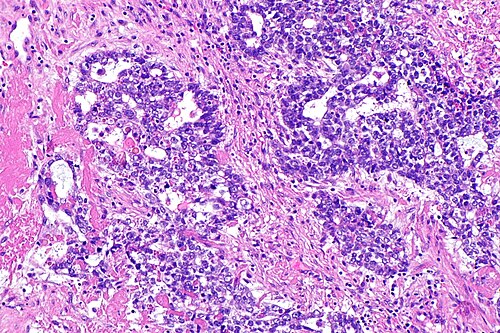

5

Diagnosis?

Choriocarcinoma - high mag.jpg

Adenomatoid tumour

Adenocarcinoma of the rete testis

Adenomatous hyperplasia of the rete testis

Benign testis

Atrophic testis

Choriocarcinoma

Embryonal carcinoma

Immature teratoma

Infarcted testis

Inflamed testis

Intratubular germ cell neoplasia

Leydig cell tumour

Lymphoma

Mature teratoma

Mixed germ cell tumour

Papillary cystadenoma of the epididymis

Seminoma

Spermatocytic seminoma

Sertoli cell tumour

Sertoli cell nodule

Testicular scar

Yolk sac tumour